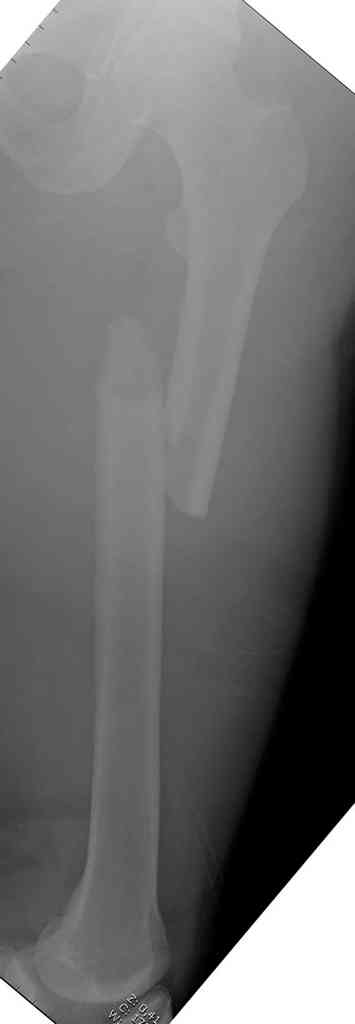

Здесь представлены снимки больного 65 лет, поступившего с диагнозом перелом

бедра после автоаварии.

В первый же день произведено антеградное штифтованием DePuy Trochanteric Nail.

На второй день (7) обнаружен пропущенный перелом,

сделаны Компьютерная Томограмма

и проведены шурурпы через и спереди штифта без удаления.

Послеоперационные снимки